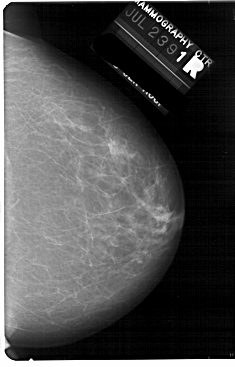

A_1738_1.LEFT_CC

LEFT_CC LINES 5491 PIXELS_PER_LINE 3481 BITS_PER_PIXEL 12 RESOLUTION 43.5 OVERLAY

FILE: A_1738_1.LEFT_CC.OVERLAY

TOTAL_ABNORMALITIES 1

ABNORMALITY 1

LESION_TYPE MASS SHAPE LOBULATED MARGINS ILL_DEFINED

ASSESSMENT 4

SUBTLETY 2

PATHOLOGY BENIGN

TOTAL_OUTLINES 1

BOUNDARY